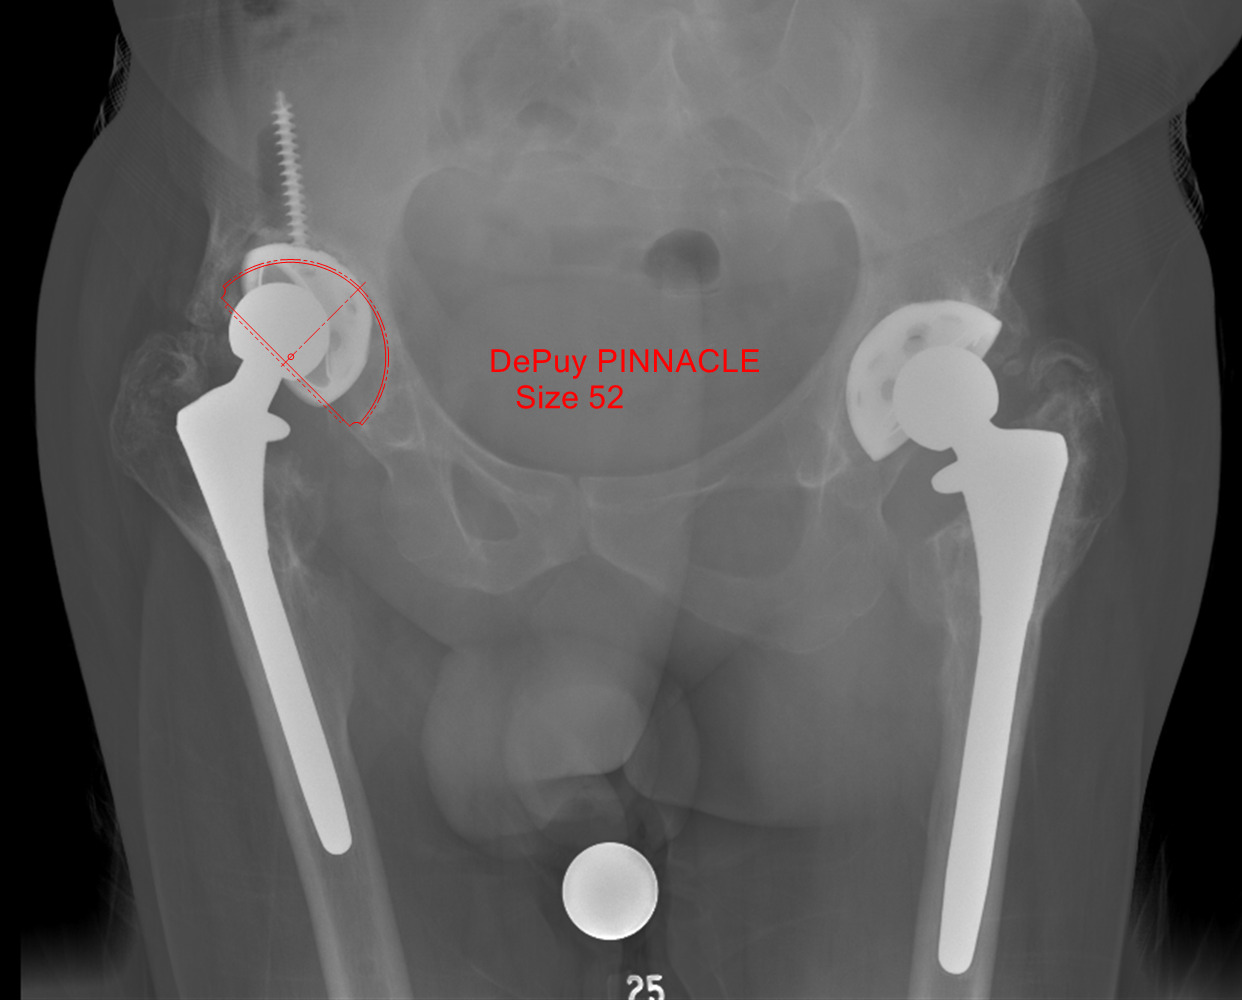

Radiographs revealed the presence of bilateral THA components, with catastrophic failure of his right acetabulum component with osteolysis and debonding of the bone implant interface (Fig. 1). Additionally, lucency of the proximal femur was noted, most likely secondary to osteolysis, and no evidence of subsidence of his femoral component was seen. Extensive heterotopic ossification (HO) of the capsule was evident on radiographs. The patient’s preoperative infection work-up was a Musculoskeletal Infection Society score of 0, including c-reactive protein and erythrocyte sedimentation rate within normal limits and negative gram stain (Parvizi et al. 2018).

The preoperative radiograph was templated using a 52 mm Pinnacle cup (Depuy Synthes, Warsaw, IN) (Fig. 2). The patient was placed supine on the Hana table (Mizuho Osi, Union City, CA). Incision was performed from the anterior half of the iliac crest to the anterior superior iliac spine, and then extended an additional 10 centimeters towards the lateral patella. Dissection was performed down to the tensor fascia lata (TFL). The TFL was released from the anterior iliac crest, and superficial dissection continued using the TFL-sartorius interval. Rectus femoris was released from the anterior inferior iliac spine, and deep dissection was performed through the rectus femoris-gluteus medius interval. No purulence was encountered. Locating the femoral neck was difficult due to the extensive HO present. The leg was placed into extension and maximum external rotation. Capsulectomy and excision of the HO was performed down to the level of the femoral neck. The prosthesis was completely encased within heterotopic bone. The hip could not be distracted or dislocated, so additional debridement was performed around the joint to remove the HO.